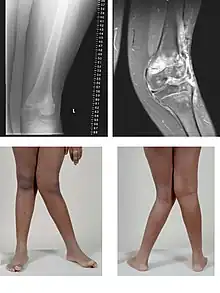

Le genu valgum (dit également « genou cagneux » ou « genou en X ») est une déviation vers l'extérieur de l'axe du membre inférieur avec saillie du genou en dedans : les deux genoux se touchent alors que les chevilles sont écartées.

Est considéré comme anormal un genu valgum asymétrique ou unilatéral, un genu valgum continuant de s'aggraver après l'âge de 4 ans, ou avec une distance intermalléolaire de plus de 8 cm chez le préadolescent. Ce n'est que dans ces cas qu'un bilan radiologique et un avis chirurgical sont indiqués[1].